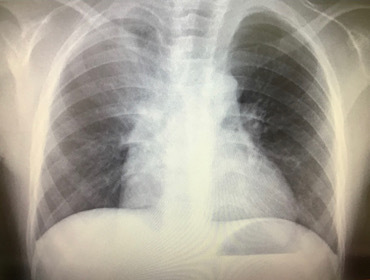

肺炎の診断

症状から肺炎を疑ったら胸部レントゲン写真を撮る必要があります。

症状や聴診器で肺の音を聴いただけでは肺炎の診断は困難です。

レントゲン写真に左右差のある白い陰影が認められたらそれは肺炎の可能性が高くなります。

マイコプラズマ肺炎のレントゲン像